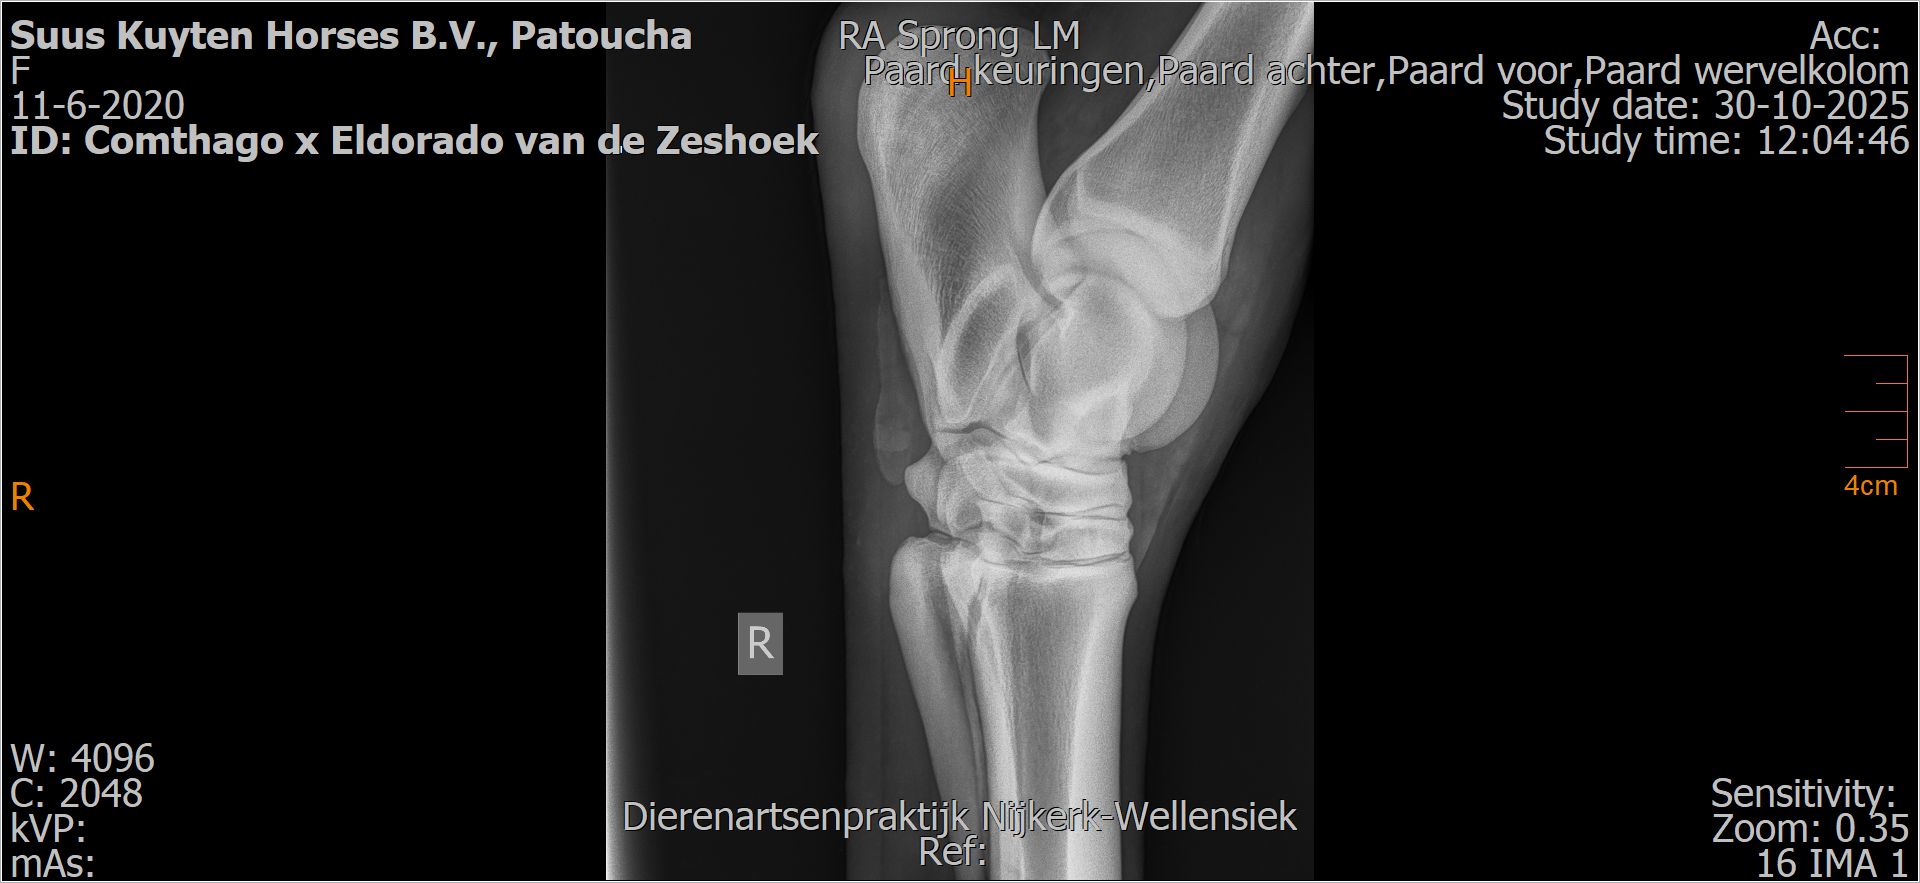

Patoucha

Leeftijd:

7

Röntgenfoto’s